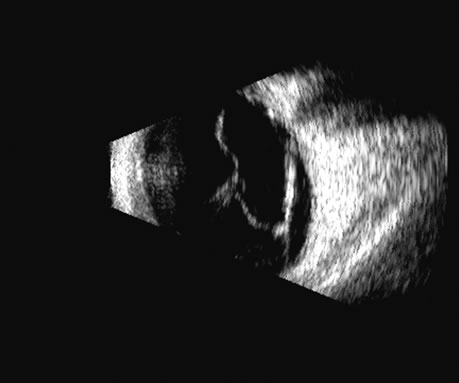

Malignant melanoma varies in its ultrasound presentation from a relatively homogeneous to heterogenous lesion on B-scan. The typical uveal melanoma absorbs sound so that the posterior section is relatively less echoic than the anterior aspect, producing a gradually decreasing amplitude, often to baseline on the A-scan (Fig. 21).

Fig. 21. An ocular tumor at the posterior pole showing the smooth convex border and solid internal reflectants typical of a melanoma.